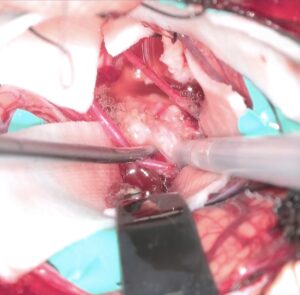

手術は通常通り行われ、顔面神経の麻痺を起こさずに摘出は終了し、うまくいったと考えていました。しかし術後より覚醒障害が続き、強い小脳腫脹を生じたため、術後脳室ドレナージ術、バルビタール麻酔療法、気管切開まで行い急性期を乗り切りました。術前より下肢静脈血栓症を合併していたことと、Petrosal veinが通常より広範囲の静脈環流を行っていたためと考えられます。現在、覚醒し、四肢が動くようになってきました。

手術は通常通り行われ、顔面神経の麻痺を起こさずに摘出は終了し、うまくいったと考えていました。しかし術後より覚醒障害が続き、強い小脳腫脹を生じたため、術後脳室ドレナージ術、バルビタール麻酔療法、気管切開まで行い急性期を乗り切りました。術前より下肢静脈血栓症を合併していたことと、Petrosal veinが通常より広範囲の静脈環流を行っていたためと考えられます。現在、覚醒し、四肢が動くようになってきました。